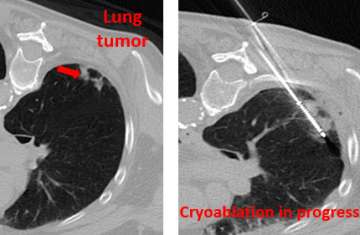

An interventional radiologist uses CT to guide a thin needle (cryoprobe) into the cancerous tissue. The probes are hollow and allow for circulation of gas. Argon gas is then pumped into the cryoprobe in order to freeze and destroy the cancer tissue. Cancer cells die immediately with exposure to ice. Probes are removed at the end of the procedure.